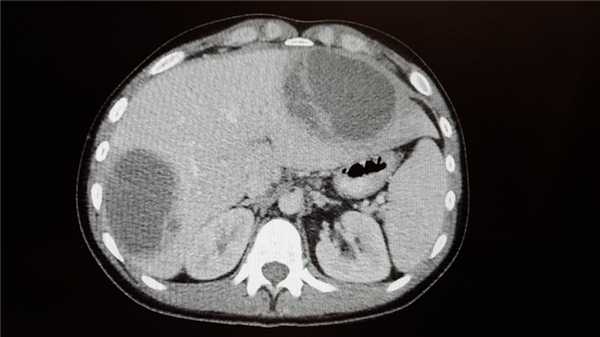

Абсцесс печени чаще всего возникает в результате распространения инфекции по сосудистому руслу из воспалительных очагов других органов или тканей брюшной полости (аппендицит, холангит, язвенный колит). Абсцессы могут быть одиночными или множественными. Для заболевания характерна высокая температура, озноб, боль и тяжесть в области печени, увеличение ее размеров.

Абсцесс в печени